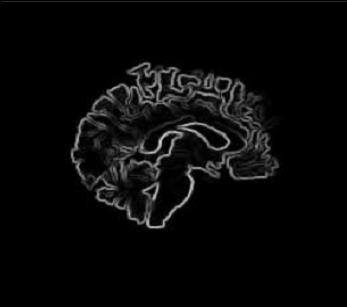

| our model | ![]() | ![]() | ![]() |

| fluid model | ![]() | ![]() | ![]() |

| deformed template | difference image before registration | edge map |

| slice 36 |

| |||

| slice 39 | ||||

| slice 54 | ||||

| slice 60 | ||||

| template | coarse deformed template | fine deformed template | target | |